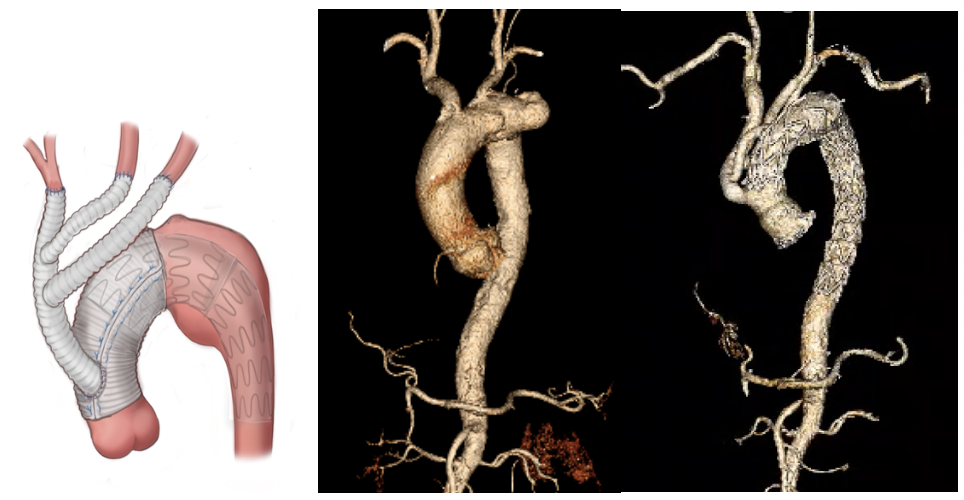

病例一:主动脉A型夹层行分支优先的孙氏手术

A型主动脉夹层,分支优先的孙氏术后。在体外循环前完成主动脉弓三分支的重建,在手术中保证全脑灌注,大大降低了脑部并发症的发生率,提高了停循环温度,减少了体外循环时间及心脏缺血时间。